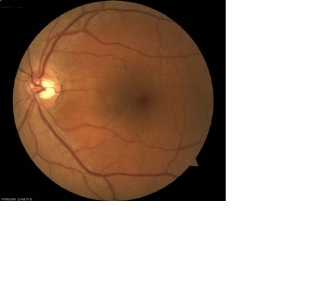

Fundus Appearance - Clinically, there is a localized retinal elevation (detachment). There may also be a detachment of the outermost layer of the retina called retinal pigment epithelium (RPE). There may be some small yellow spots in the area of detachment. There may be other areas with changes in pigmentation which are believed to correspond to previous CSR episodes

csr1 csr3

csr2